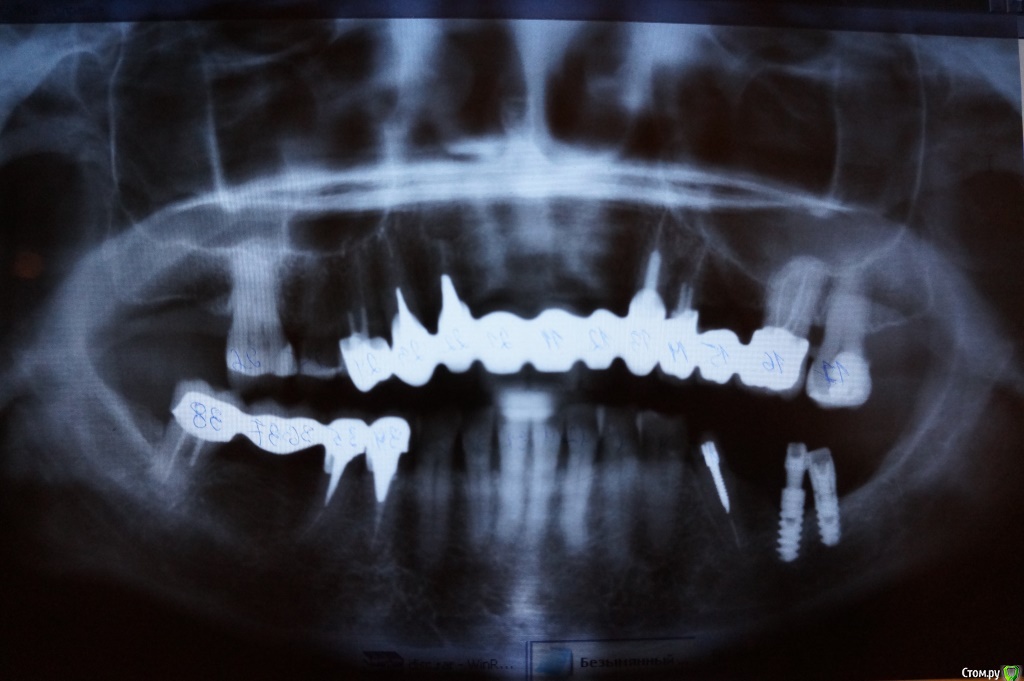

Evitavonni Опубликовано 26 января, 2015 Поделиться Опубликовано 26 января, 2015 Уважаемые доктора стоматологи, необходимо ваше мнение - что делать? Надеюсь, что в прилагаемой панораме что-то можно рассмотреть. В данный момент все металлокерамические конструкции легко снимаются, каждый день дважды снимаю, чищу и фиксирую на 16 и 24 верхний, на 38-й нижний на крем корегу. 46-й имплант выпал. Вкладки все рассосались, короче, ситуация ужасная. Почти решилась на базальную имплантацию, но почитав отзывы на форуме, поняла, что не всему можно верить насчет чудес, о которых пишут о них на некоторых сайтах клиник. Действительно ли, что это чистый бизнес без гарантии и не стоит рисковать своим здоровьем? Можно ли обойтись без синус-лифтинга и подсадки кости при двухэтапной имплантации? Ссылка на комментарий

diesel87 Опубликовано 26 января, 2015 Поделиться Опубликовано 26 января, 2015 Не той стороной выложили снимок 1 Ссылка на комментарий

Evitavonni Опубликовано 29 января, 2015 Автор Поделиться Опубликовано 29 января, 2015 Не той стороной выложили снимок Уважаемый доктор! Снимок переложила. Подскажите пожалуйста, что в моем случае более оптимально на верхней челюсти - "all on four" или все-таки двухэтапная имплантация, которая наверно, потребует синус-лифтинга? Очень привлекает первое - короткие сроки, стоимость.На нижней без пластики тоже не обойтись? Каково Ваше мнение? Спасибо. Ссылка на комментарий